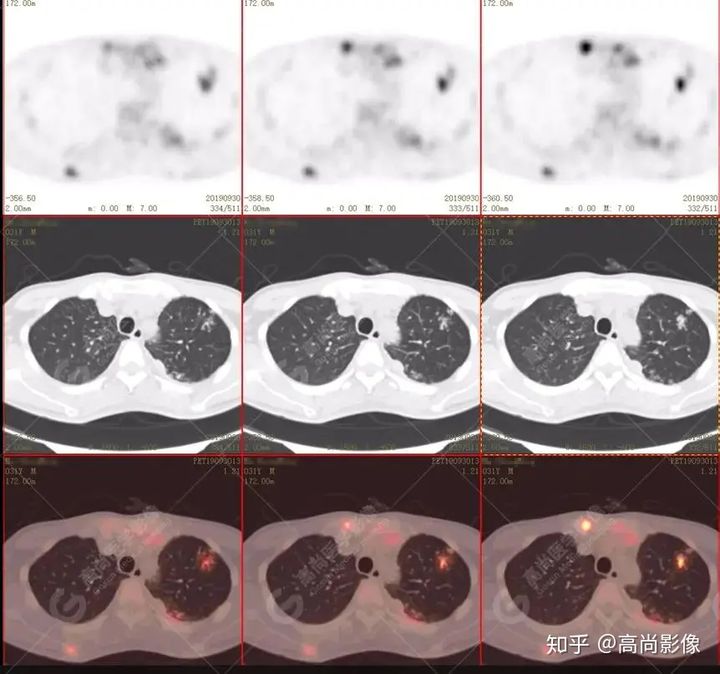

左肺上葉尖后段及下葉背段多發(fā)簇狀斑點狀高代謝灶

左側(cè)胸膜結(jié)節(jié)樣增厚,代謝不同程度增高

【PET/CT提示】雙肺、左側(cè)胸膜多發(fā)結(jié)節(jié)影,全身多處骨質(zhì)破壞,全身多發(fā)淋巴結(jié)腫大,代謝攝取不均勻性增高。

特征:肺部病灶簇狀分布,上葉尖段及下葉背段為著;腫大淋巴結(jié)分布不對稱,無融合、中央有壞死改變,與淋巴瘤、轉(zhuǎn)移瘤等有一定的鑒別診斷意義;

好發(fā)上葉尖后段及下葉背段(血氧飽和度豐富);